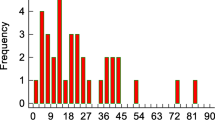

Statistical analyses were performed using the Statistical Package for the Social Sciences (Version 28.0). Educational level was scored using the Dutch classification system ranging from (1) = no primary school, to (7) = university (Verhage, 1964). Descriptive statistics were used to describe demographic and clinical characteristics. Brain volumes were normalized for age, sex, and head size (percentile values). cNeuro cMRI has internal cut-off values to identify atypical brain volume values, compared to the on-board normative database. Cerebral parenchymal volume values below the 10th percentile were categorized as ‘lower’. Ventricular volumes above the 90th percentile were categorized as ‘higher’. Normality assumptions were checked. To test for differences in volume measurements between the total SAH group and HC2, Mann-Whitney U and independent t-tests tests were used. Raw scores for neuropsychological measures were compared between the total SAH patient group and HC1, using Mann-Whitney U and independent t-tests. Subsequently, raw scores of all neuropsychological measures were transformed into z-scores based on sex, age, and education matched normative data (Lezak et al., 2004). Then, z-scores were computed based on raw scores, averaged within each cognitive domain (excluding social cognition). These z-scores were then compared between patients with and without low cerebral parenchymal volumes or high ventricular volumes in specific brain regions, using Mann-Whitney U and independent t-tests. A significance threshold of p < 0.05 (two-tailed) was applied, with Bonferroni-Holm corrections for multiple comparisons.

In Table 2, percentages of patients and HC with lower or, in case of the ventricles, higher volumetric measurements as compared to the on-board normative database are depicted for multiple brain regions. In both patients with aSAH and anSAH, lower regional cerebral parenchymal volume was most profound in the frontal lobe. Higher ventricular volume was most frequent in the lateral ventricle - temporal horn and fourth ventricle after aSAH and in the lateral ventricle - frontal horn/body/occipital horn after anSAH.